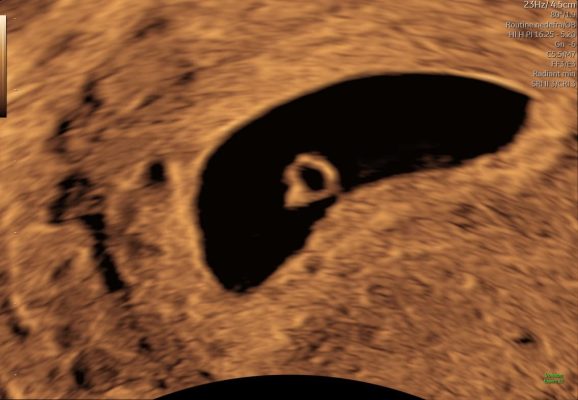

Tidlig scanning uge 6 – foster i livmoderen

Tidlig scanning uge 5–6 – blommesæk i livmoderen

Eksempel på ultralyd i uge 5–6. Det er normalt, at ikke alle strukturer kan ses på dette tidspunkt.

Kort ultralydssekvens fra uge 6 hvor der kan ses blommesæk og tidligt fosteranlæg.

Ultralydsscanning uge 7 – hjerteblink

Ultralydsscanning uge 8 – lille foster i livmoderen

Eksempel på ultralyd i uge 7–8. Hjerteblink kan ofte ses, men synligheden varierer.

Kort ultralydssekvens fra uge 7, hvor hjerteaktivitet og tidlig bevægelse kan ses.